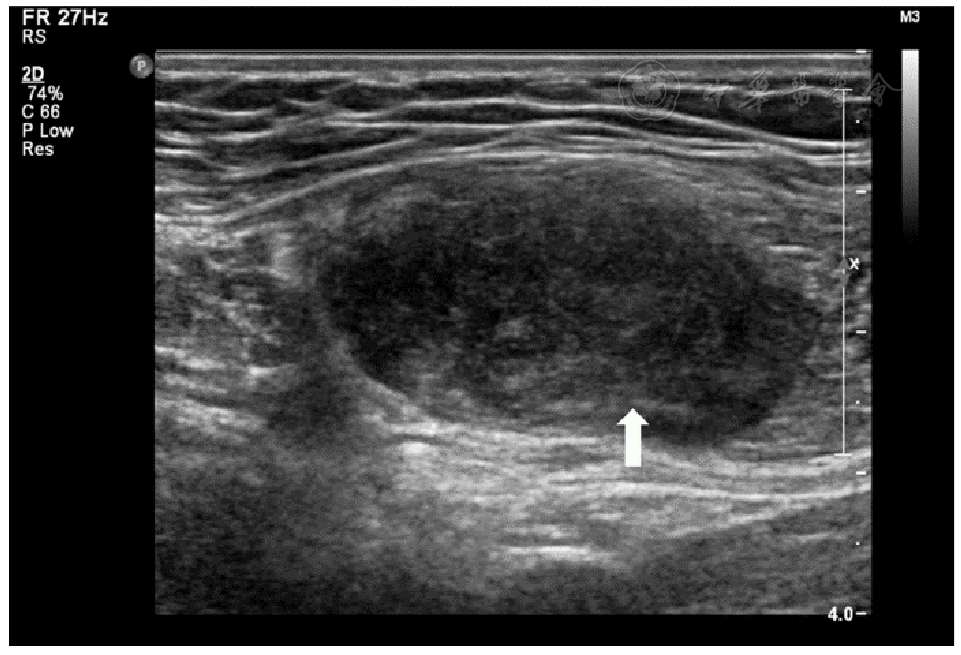

图2 腹壁型侵袭性纤维瘤病的"梳子征"表现注:病灶内部回声不均,呈高、等、低回声混杂相间的表现(箭头所示,长轴的二维灰阶超声图像,探头频率5~12 MHz)。

10例腹壁侵袭性纤维瘤病患者年龄29~64岁,中位年龄34.5岁;女性患者9例,男性患者1例。10例患者均为单发病灶,且均发生于腹壁肌层。超声表现:低回声为主(10/10例,100%),沿肌层平行生长(10/10例,100%),沿肌层水平方向浸润性生长(7/10例,70%),在垂直于肌层的方向上病灶边界清晰(10/10例,100%),内部回声不均匀(9/10例,90%),内部未见钙化及液性暗区(10/10例,100%)。

The ages of the 10 patients with aggressive fibromatosis of the abdominal wall ranged from 29 to 64 years (median age 34.5 years), including 9 female patients and 1 male patient. All 10 patients had single lesions and all occurred in the muscular layer of the abdominal wall. The ultrasound manifestations were mainly hypoechoic (10/10 cases, 100%), parallel growth along the muscular layer (10/10 cases, 100%), infiltrative growth along the horizontal direction of the muscular layer (7/10 cases, 70%), clear lesion boundaries in the direction perpendicular to the muscular layer (10/10 cases, 100%), and uneven internal echoes (9/10 cases, 90%). No calcification or liquid dark areas were observed internally (10/10 cases, 100%).